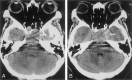

Results: Overall, the agreement rate was 91%; the insignificant disagreement rate, 7%; and the significant disagreement rate, 2%. The level of training had a significant (P =.032) effect on the rate of agreement; upper-level residents had higher rates of agreement than those of more junior residents. There were 62 false-negative findings. The most commonly missed findings were fractures (n = 18) and chronic ischemic foci (n = 12). The most common false-positive interpretations involved 10 suspected intracranial hemorrhages and suspected fractures.

Conclusion: The level of resident training has a significant effect on the rate of disagreement between the preliminary interpretations of emergency cranial CT scans by residents and the final interpretations by neuroradiologists. Efforts to reduce residents' errors should focus on the identification of fractures and signs of chronic ischemic change.